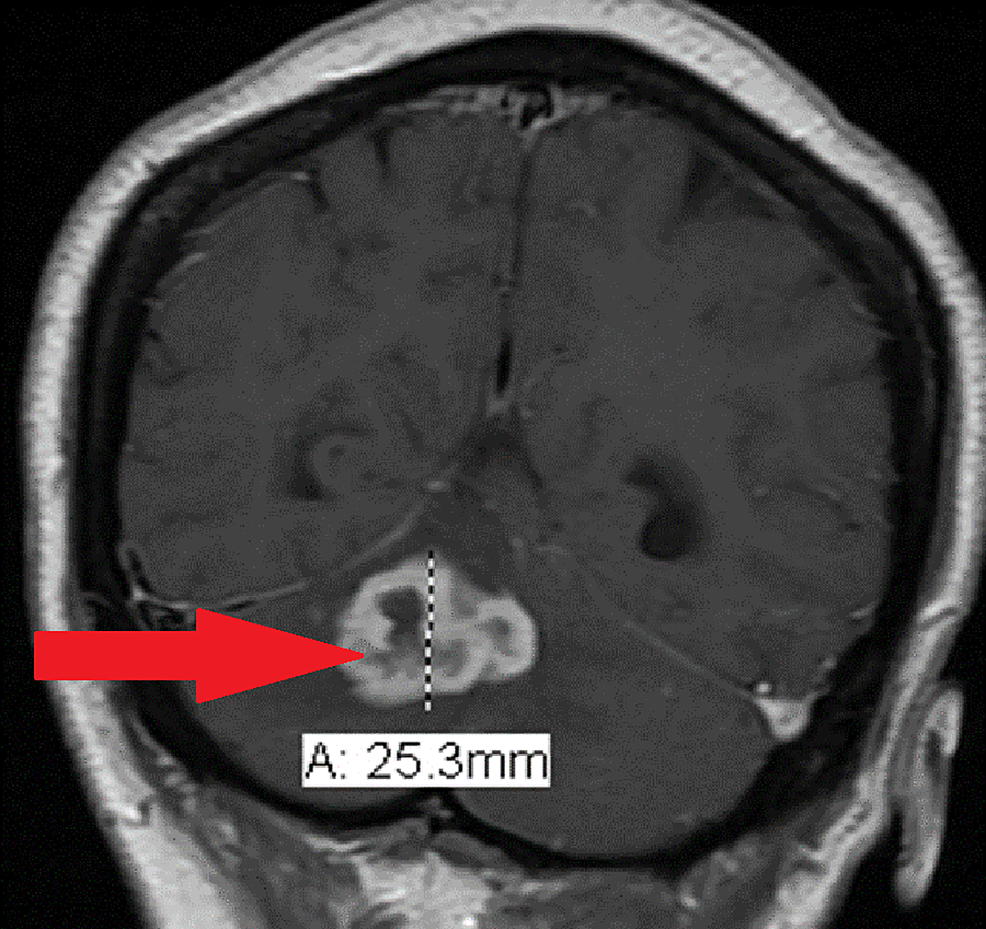

Ring enhancing lesion is a radiological sign whereby on the image there is a lesion with area of hypodensity surrounded by a bright rim from contrast.

There is a useful mnemonic for differential diagnosis of ring enhancing lesions magical doctor. The term ring enhancing refers to lesions which develop a circular doughnut like rim of enhancement after contrast administration. Cerebral abscess tuberculoma neurocysticercosis metastasis glioblastoma subacute infarcthemorrhagecontusion demyelination incomplete ring tumefactive demyeli.

A ring enhancing lesion is an abnormal radiologic sign on mri or ct scans obtained using radiocontraston the image there is an area of decreased density see radiodensity surrounded by a bright rim from concentration of the enhancing contrast dyethis enhancement may represent breakdown of the blood brain barrier and the development of an inflammatory capsule. The differences between enhancing and nonenhancing lesions in mri are obvious.